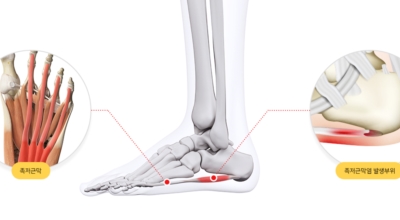

족저 근막염이란?

족저 근막이란 발가락 시작지점부터 발뒤꿈치뼈까지 발바닥 전체를 감싸고 있는 두꺼운 막을 말해요. 족저 근막은 발바닥 아치를 보존시켜 발바닥이 지면을 내딛음으로써 생기는 쇼크을 흡수하는 중요시되는 역할을 수행하고 있어요. 이 족저 근막에 일차적으로 서서히 조직 훼손이 일어나고 계속적인 활동에 의하여 염증이 커지면서 발 뒤꿈치 부근 통증을 일으키게 되는데 염증은 무리하고 반복적인 동작, 많은 활용으로 마찰에 의해 발생해요.

족저 근막염은 염증에 의한 훼손 및 통증을 유발하는 질환인데요 족저 근막염 증상은 동일한 발뒤꿈치 통증 하글런드 병변의 기형으로 알려져 있으고 아킬레스 건과 연관이 깊다고 해요. 특히 근육이 덜 풀린 아침 시간 대는 보행 시 날카롭고 바늘로 찌르는 듯한 심한 통증을 느끼게 된다고 해요. 하지만 아침 시간 대를 지나 오후에 접어들면서 일정 양 통증은 서서히 감소하기 시작한다고 하는데요 초기 증상이 나타난다면 필수로 전문의를 찾아 조기치료하는 것이 바람직해요.